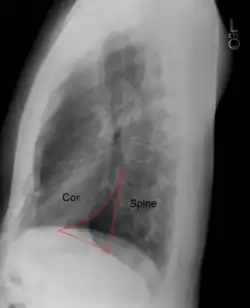

Der Holzknecht-Raum oder Retrokardialraum (Abk. RCR, lat.: Spatium retrocardiale) ist ein Raum zwischen der hinteren Herzkontur (die dem linken Vorhof und Ventrikel entspricht) und der Wirbelsäule, auf seitlichen Röntgenaufnahmen des Brustkorbs. Er wurde nach Guido Holzknecht (1872–1931), einem Pionier der Radiologie und Universitätsprofessor in Wien, benannt.

Der Holzknecht-Raum ist bei Herzkrankheiten, die mit einer Vergrößerung der linken Herzhöhlen einhergehen, eingeengt, etwa bei Herzklappenfehlern. Er kann auch bei Gesunden schmal sein, z. B. bei Trichterbrust.